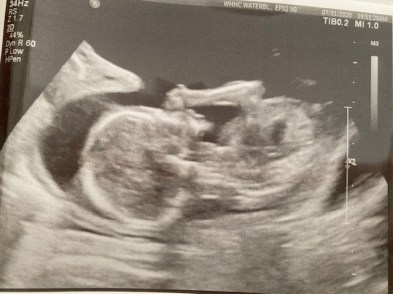

he looks good

to keep my child alive